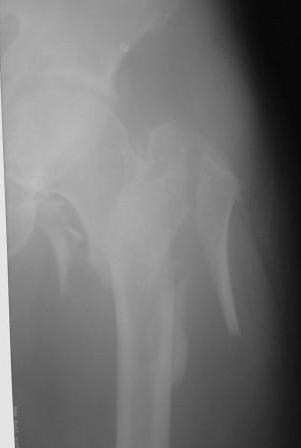

Re: Чрезвертельный перелом бедра

По нашему мнению линия перелома проходит вверху через латеральный отдел шейки бедра, вертельная область состоит из нескольких фрагментов. В таких условиях применить DHS или дистальную бедренную пластину LCP представляется нам сомнительным. Закрытый остеосинтез проксимальным гамма-гвоздем или PFNa невозможен т.к. нет ЭОПа.

Возможно открытый остеосинтез гвоздем PFNa?

Прилагаю Р-ы на вытяжении.